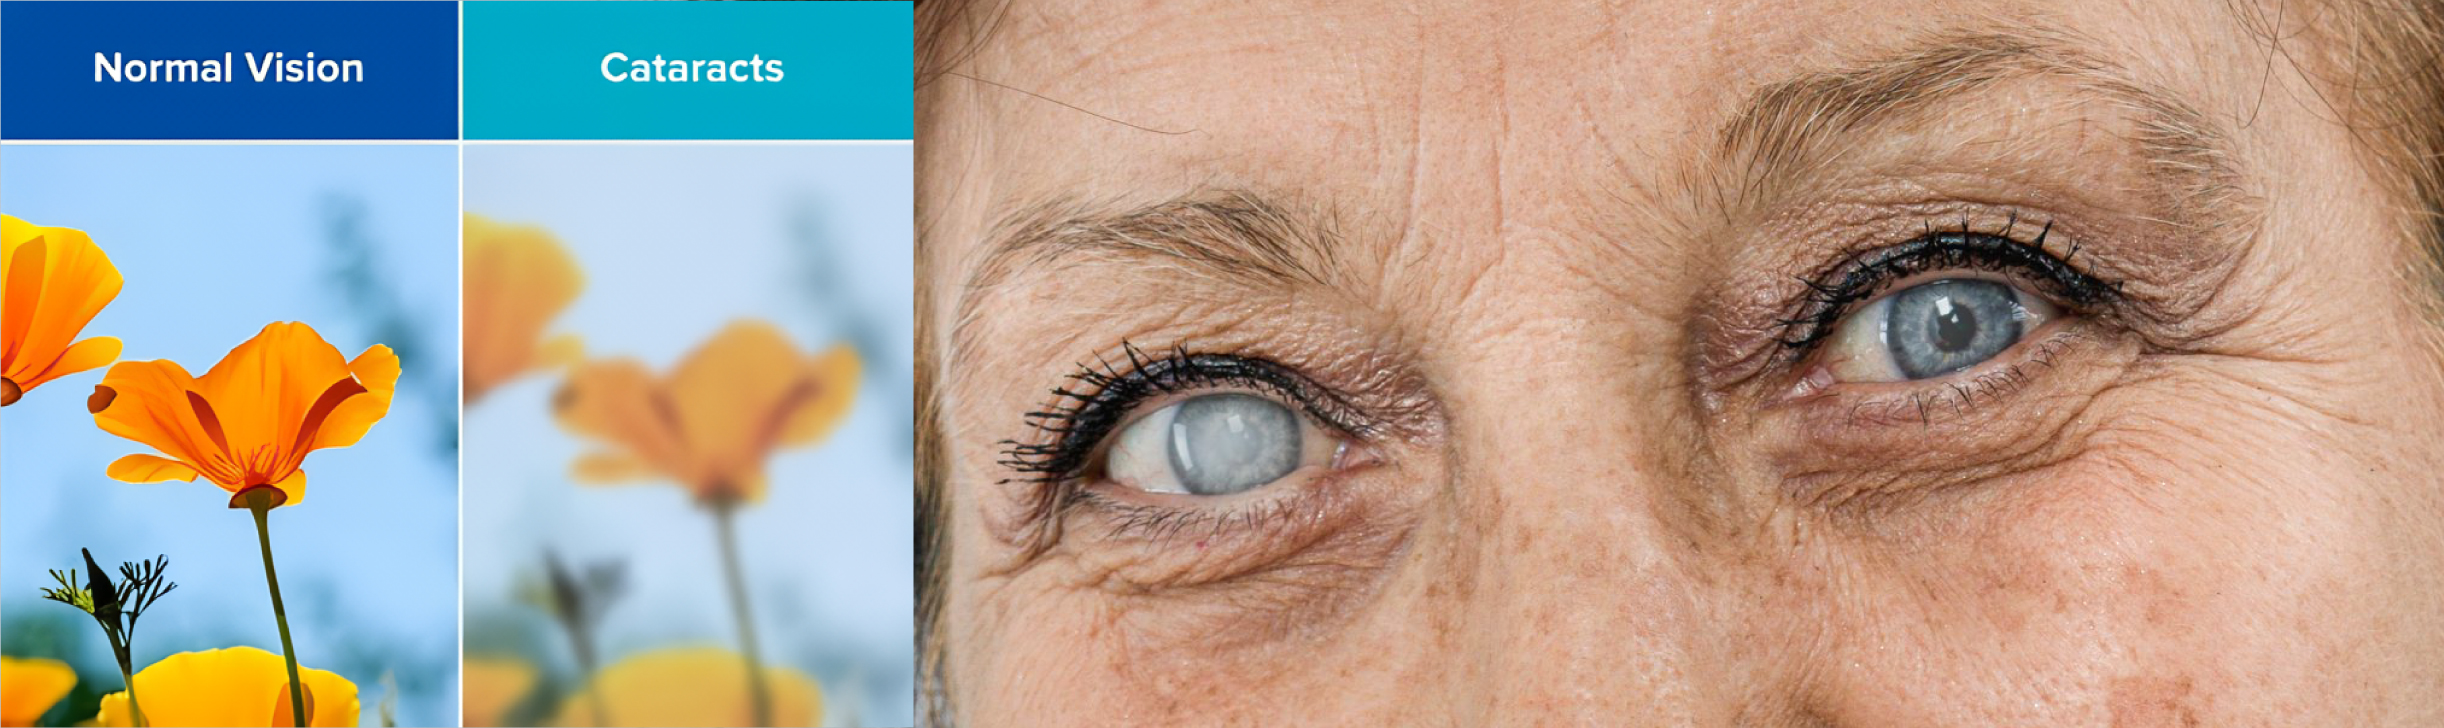

白内障

白内障是眼睛晶状体的自然混浊,该晶状体位于虹膜和瞳孔后方,正常情况下将光线聚焦到视网膜上以获得清晰的视觉。这种混浊是由于晶状体内的蛋白质聚集在一起,阻挡并散射光线,从而导致视力模糊、眩光、颜色褪色以及夜间视力困难等症状。虽然衰老是白内障最常见的原因,但其他促成因素包括糖尿病、眼部损伤、长期使用皮质类固醇以及过度暴露于紫外线(UV)光。白内障通常发展缓慢,初期可能不会干扰视力,但最终会发展为严重的视力障碍。对于白内障最有效的方法是手术干预,在此过程中,混浊的晶状体被移除,并替换为清晰的人工晶状体,从而恢复清晰的视力。

中医将白内障称为“圆翳内障”,认为其发病机制与多种因素有关。首先,年老体弱、肝肾不足会导致精血亏损,无法充分滋养晶状体,从而引起混浊。其次,阴血不足会产生虚热,虚热上炎灼伤晶状体,也会导致混浊。此外,老年人脾虚气弱,运化功能减退,精微物质无法有效输布,晶状体得不到充足营养,或体内水湿过多上泛至晶状体,以及肝热上扰目窍,均可导致晶状体逐渐混浊。对于早期白内障患者,中医可通过中药控制或减缓病情发展。然而,当晶状体混浊程度较重,影响到日常生活或工作时,应考虑白内障手术。